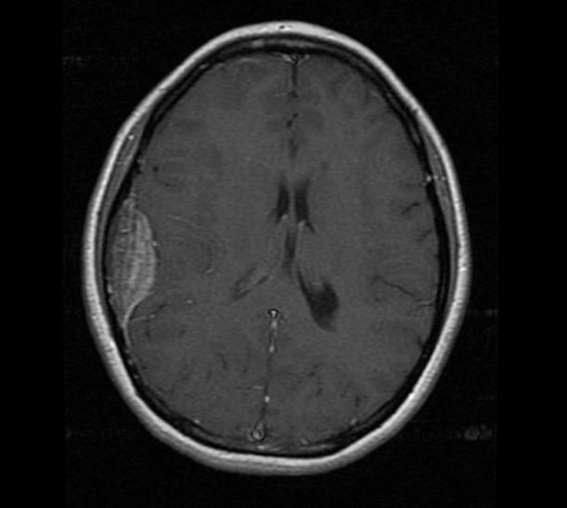

Caso 2. Mujer de 26 años al momento del diagnóstico. Consulta por cefalea crónica y se realiza resonancia magnética de cerebro con contraste que informa proceso expansivo extraaxial sésil, biconvexo frontoparietotemporal derecho con efecto de masa moderado de 4,9 x 2 x 5,4 cm en sentido cefalocaudal, transverso y anteroposterior, sugerente de meningioma (Figura 1). Se realiza resección quirúrgica del tumor con craniectomía parcial. La biopsia informa tejido meníngeo y fragmento óseo infiltrados por tumor linfoide compatible con linfoma linfocítico de células B pequeñas (Figura 2), con estudio inmunohistoquímico positivo en células tumorales para CD20, CD43, CD45Ro, CD79a y Bcl-2 y focal para CD5 y CD23 y negativa para ciclina D1 y CD10, con un Ki-67 positivo en 1% (Figura 3). La tomografía computada de tórax, abdomen y pelvis no demuestra signos de compromiso por linfoma. La biopsia e inmunofenotipo de médula ósea no muestran infiltración por células con fenotipo de LLC. El perfil bioquímico es normal. El hemograma muestra una anemia normocítica leve (Hb 10 g/dL) con velocidad de eritrosedimentación (VHS) levemente elevada (57 mm en la primera hora). Se realiza radioterapia localizada con 36 Gy. Luego de 5 años de seguimiento permanece sin evidencia de recidiva.

El linfoma linfocítico del SNC representa un tipo de LPSNC de bajo grado que, por su curso clínico insidioso, es de difícil diagnóstico, en relación al resto de los casos que se presentan de forma más agresiva(4). Asimismo, la apariencia de la neuroimagen puede ser poco habitual simulando otras lesiones(3), por lo cual existen diversos diagnósticos diferenciales de naturaleza benigna y maligna(5). Dentro de ellas, destaca el meningioma, que representa el tumor primario más común del cerebro y la médula espinal, siendo el 33,8% de todos los tumores diagnosticados del SNC(6). El diagnóstico se establece por hallazgos radiológicos característicos de una masa extra-axial supratentorial con una cola dural que es típicamente isodensa en la tomografía computarizada (TC) e isointensa en imágenes de resonancia magnética ponderada T1 y T2, y aumenta en intensidad con gadolinio como en uno de nuestros casos (Figura 1). Otros diagnósticos diferenciales incluyen enfermedades desmielinizantes, como la esclerosis múltiple, y gliomas(3).

Figura 1. Resonancia magnética caso 2. Corte transversal T1 con gadolinio.